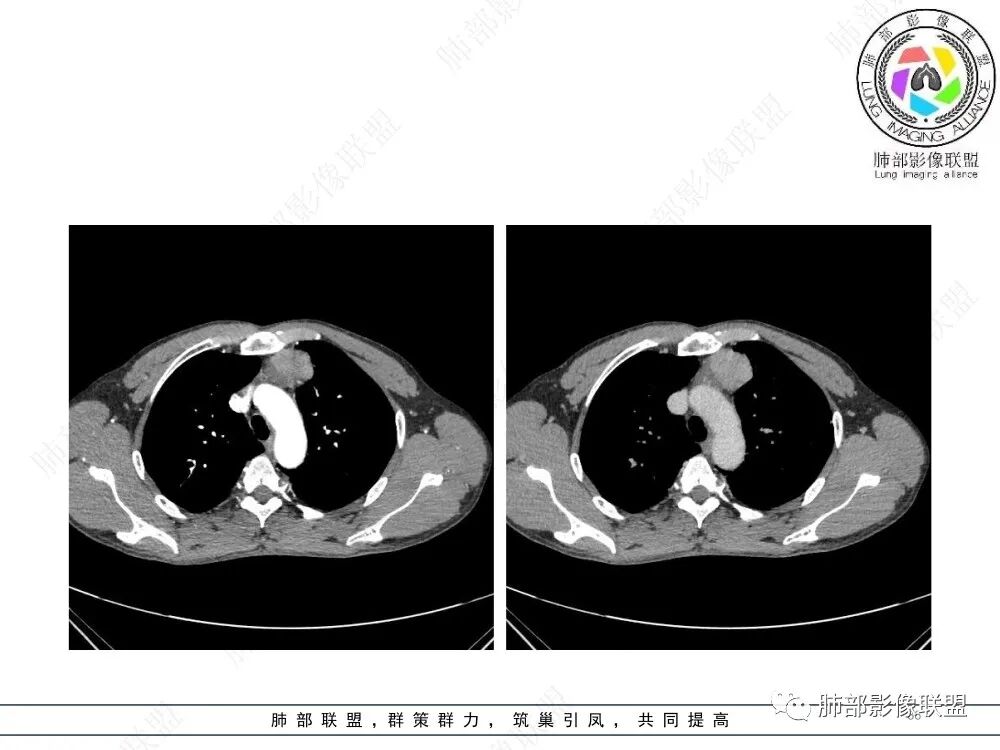

放射小白:男性47岁,前纵隔团块状占位,边界尚清,增强中度强化,内部疑似纤维分隔,常规考虑胸腺瘤可能(A/AB型),鉴别类癌、CD。

瑞欣:中年男性,检验未见明显异常,前纵隔软组织快影,边界清,可见明显强化,首先考虑胸腺瘤,鉴别淋巴瘤,畸胎瘤,生殖细胞瘤。

金豆:晨读:定位前纵隔,膨胀性生长,质地中等,边界清,有浅分叶,中等强化,似乎有裂隙低密度,常规胸腺瘤(B1)。

Yishion:晨读:纵隔占位,偏侧生长,边界清楚,有浅分叶,强化明显,其内似见纤维分隔,常规考虑胸腺瘤(AB型)。

蓝天白云:晨读:47岁男,前纵隔占位,边界清,有浅分叶,中等强化,胸腺瘤(B1)。

宇宙:前纵膈偏左类圆形肿块,边界清晰光整,与大血管脂肪间隙清,密度均匀,轻中度强化,考虑胸腺瘤,A型?鉴别胸腺癌。

玫:男,47岁,咳嗽,咳痰一年,前纵隔软组织密度肿块影,边界清晰,内密度均匀,增强扫描轻度强化,考虑胸腺瘤可能。

2、影像特点:前纵隔偏左侧软组织影,密度相对均匀,未见明显包膜钙化及实质内钙化,局部边缘浅分叶,周围脂肪间隙密度增高、浑浊,未见侵犯大血管、未见纵隔内淋巴结转移、未见侵犯心包内结构、未见胸膜转移结节、未见肿块沿着纵隔胸膜蔓延,未见胸腔积液。增强后动脉期不均匀强化,未见明显纤维分隔。